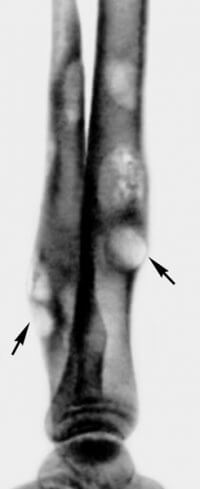

Развивается при проникновении инфекции из внешней среды, распространении микробов из соседнего гнойного очага либо при пиемии. Как правило, возбудителям гнойного воспаления надкостницы являются стафилококки или стрептококки. Чаще всего отмечается данный вид периостита в длинных трубчатых костях – например, большеберцовой, бедренной или плечевой, а если виновником патологии стала пиемия, то возможно формирование множественных очагов воспаления надкостницы.

Начальный этап развития гнойного периостита характеризуется воспалением надкостницы, появлением в ней серозного или фибринозного экссудата – вот он-то как раз и превращается потом в гной. Внутренний слой надкостницы пропитывается гноем и начинает отделяться от кости, в образовавшемся пространстве между костью и надкостницей формируется субпериостальный абсцесс. Дальнейшее развитие рассматриваемого заболевания вариативно:

- гной разрушает участок надкостницы и проникает в мягкие ткани, что приводит к формированию параоссальной флегмоны. Эта флегмона может в будущем либо распространиться в мягкие ткани, либо вскрыться наружу через кожу;

- гной отслаивает большой участок надкостницы, что приводит к ограничению питания кости и образованию поверхностного некроза.

Обратите внимание: гнойное воспаление надкостницы может иметь неблагоприятное развитие, и тогда гной будет проникать в костномозговую полость, что провоцирует развитие остеомиелита.